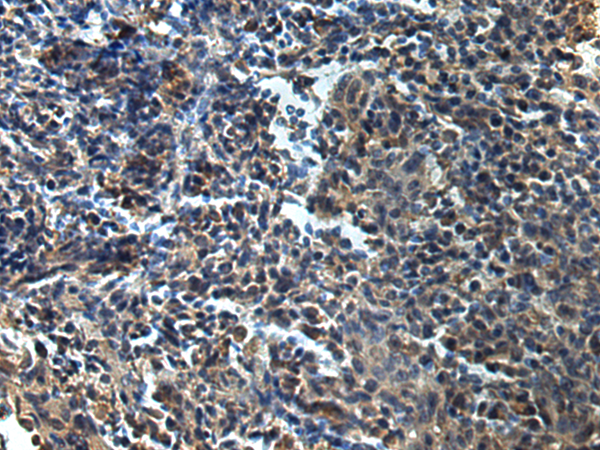

分类: 科研抗体货号: P12851别名: AMOG应用: WB,IHC反应种属: Human, Mouse, Rat